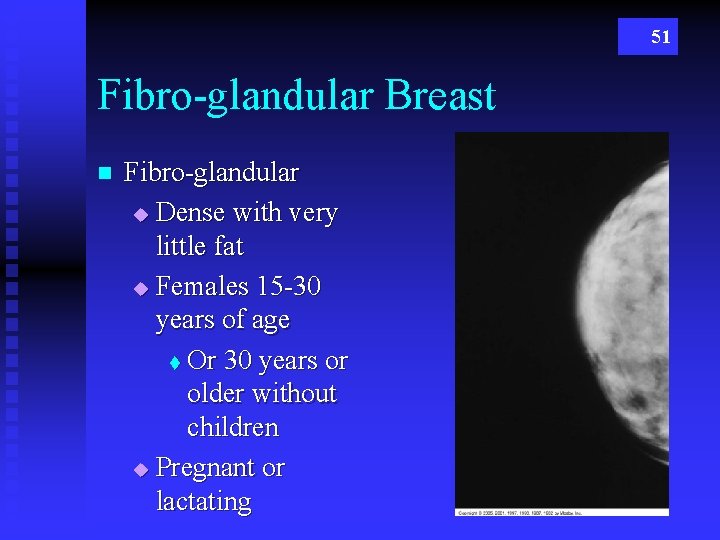

51 Fibro-glandular Breast n Fibro-glandular u Dense with very little fat u Females 15 -30 years of age t Or 30 years or older without children u Pregnant or lactating